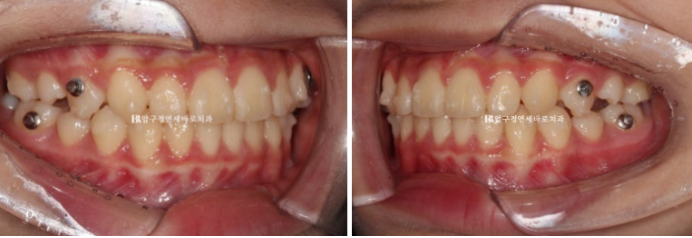

24.01

아래는 유지가 잘 되어서 문제가 없었으니 위 송곳니 날 자리가 부족해서 덧니처럼 회전이 된 채 내려오는 것이 보입니다.

이런 부분 때문에 인비절라인 퍼스트는 18개월의 보증기한을 두고 있습니다.

예상과 벗어난 부분을 고치기 위해서입니다.

보증기간 내에 발견된 문제점은 얼마든지 해결이 가능합니다.

재제작에 들어갔고 24년 7월까지, 6개월간 한 세트의 추가장치를 더 꼈습니다.